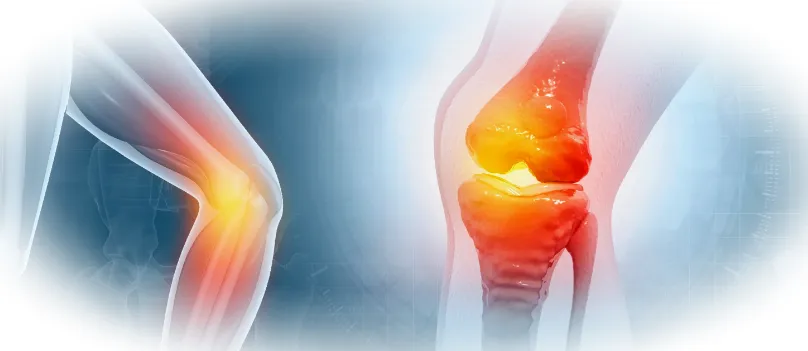

Многие люди не придают значения первым тревожным признакам — легкому дискомфорту в коленях, утренней скованности или негромкому хрусту при движении. Часто такие симптомы воспринимаются как следствие переутомления или возрастных изменений. Однако именно эти незначительные ощущения нередко сигнализируют о начале воспалительного процесса в суставах, который без лечения может привести к серьезным нарушениям.

Что происходит при воспалении суставов

Воспаление суставов — это естественная защитная реакция организма на повреждение тканей или проникновение инфекции. В этот период в области поражения появляется отек, покраснение, боль и ощущение жара. Постепенно в процесс вовлекаются хрящевые структуры, связки, мышцы и синовиальная жидкость, обеспечивающая легкое движение суставных поверхностей.

Если не начать лечение вовремя, хрящ начинает разрушаться, утрачивая плотность и эластичность. Сустав теряет подвижность, появляется боль при малейшей нагрузке. Из-за снижения активности кровообращение в тканях ухудшается, что еще больше ускоряет разрушительные процессы.

Игнорирование воспаления суставов чревато развитием остеоартрита. В результате суставные поверхности разрушаются, деформируются, образуются костные наросты, а движения становятся затрудненными и болезненными.